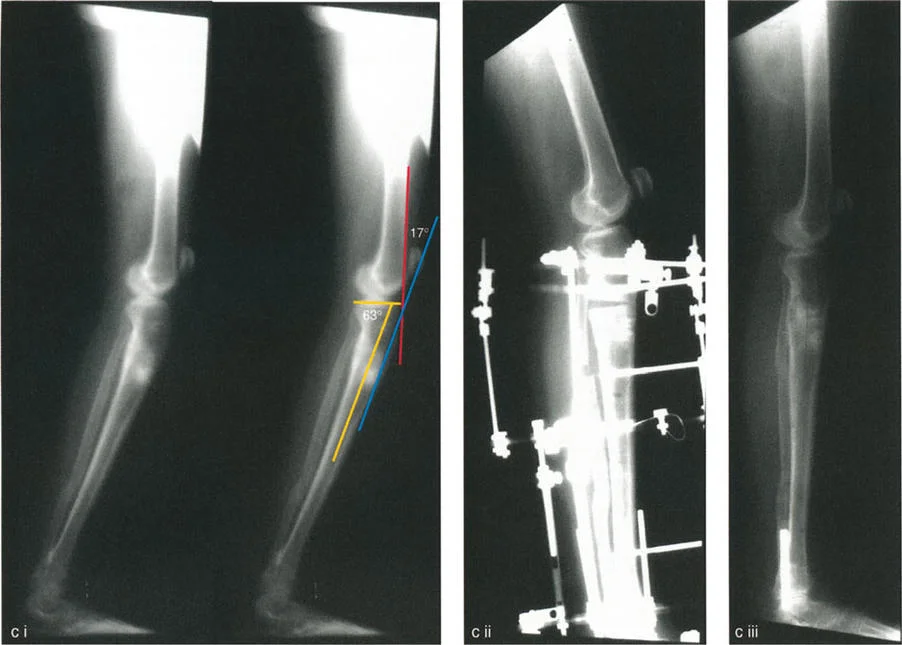

تصحيح تحدد حركة الركبة (Flexion Deformity - FFD)

تحدُّد حركة الركبة هو عدم القدرة على مد الركبة بالكامل. يمكن أن يكون سببه عظميًا أو ناتجًا عن تقلص في الأنسجة الرخوة.

- التشخيص الدقيق: يجب تحديد ما إذا كان تحدد الحركة ناتجًا عن تشوه عظمي (تقوس أمامي في الفخذ أو الساق) أو تقلص في الأنسجة الرخوة (الأوتار الخلفية، محفظة المفصل).

- قطع العظم التمديدي (Extension Osteotomy):

- إذا كان التشوه عظميًا، يتم إجراء قطع عظم تمديدي في عظم الفخذ أو الساق لتصحيح التقوس.

- التصحيح التدريجي: في حالات تحدد الحركة الشديدة أو المعقدة، قد يكون التصحيح التدريجي باستخدام التثبيت الخارجي هو الخيار الأكثر أمانًا.

تصحيح الركبة الارتدادية (Recurvatum Deformity - Hyperextension)

الركبة الارتدادية هي فرط البسط في الركبة. غالبًا ما تكون غير مصحوبة بأعراض في الأشخاص ذوي العضلات السليمة، ولكنها قد تسبب مشاكل في حالات ضعف العضلات أو التشوهات العظمية.

- التشخيص: يجب تحديد ما إذا كانت الارتدادية عظمية (تقوس خلفي في الفخذ أو الساق) أو ناتجة عن رخاوة في الأنسجة الرخوة أو ضعف عضلي.

- قطع العظم الانثنائي (Flexion Osteotomy):

- إذا كان التشوه عظميًا (تقوس خلفي)، يتم إجراء قطع عظم انثنائي في عظم الفخذ أو الساق لتصحيح الارتدادية.

- الأستاذ الدكتور محمد هطيف يشدد على أهمية عدم استخدام قطع عظم الفخذ الانثنائي لتصحيح ارتدادية الساق، والعكس صحيح، لتجنب الانزلاق الخلفي أو الأمامي للركبة.

- اعتبارات خاصة: في المرضى الذين يعانون من ضعف عضلي (مثل شلل الأطفال)، قد يحتاج التصحيح إلى فرط تصحيح بسيط (overcorrection) إلى وضعية انثناء لضمان ثبات الركبة ومنع فرط البسط غير المتحكم فيه.